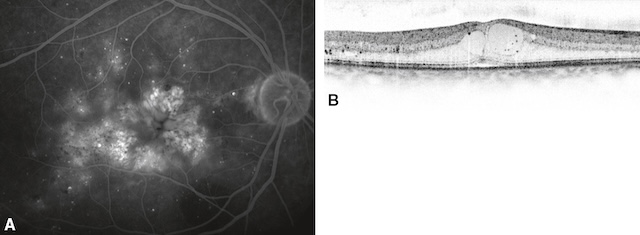

Des injections d’anti-VEGF (ranibizumab, aflibercept) sont efficaces pour réduire l’œdème maculaire et maintenir ou améliorer l’acuité visuelle durant de nombreux mois. Ce traitement est indiqué en cas d’œdème atteignant le centre de la macula et associé à une baisse de l’acuité visuelle (fig. 20.16).

Noter la disparition des espaces microkystiques et le retour à un profil maculaire proche de la normale.

L’image A en tomographie en cohérence optique (OCT) révèle un œdème maculaire cystoïde typique, avec plusieurs cavités hypo-réflectives bien délimitées dans l’épaisseur de la rétine centrale, traduisant une accumulation de liquide intrarétinien. Les contours fovéolaires sont bombés, et l’épaississement rétinien est net. En B, un mois après l’injection intravitréenne d’un anti-VEGF, la rétine apparaît nettement asséchée. Les espaces kystiques ont disparu, la fovéa retrouve une configuration concave normale, et l’épaisseur rétinienne est considérablement réduite. Cette évolution témoigne d’une réponse favorable au traitement avec une résorption quasi complète du liquide.